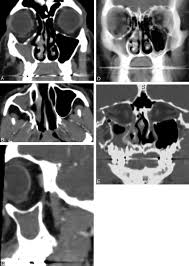

Figure 1 From Bilateral Silent Sinus Syndrome Case Report And Surgical Solution Semantic Scholar

Figure 6 From Bilateral Silent Sinus Syndrome Case Report And Surgical Solution Semantic Scholar

Figure 2 From Bilateral Silent Sinus Syndrome Case Report And Surgical Solution Semantic Scholar